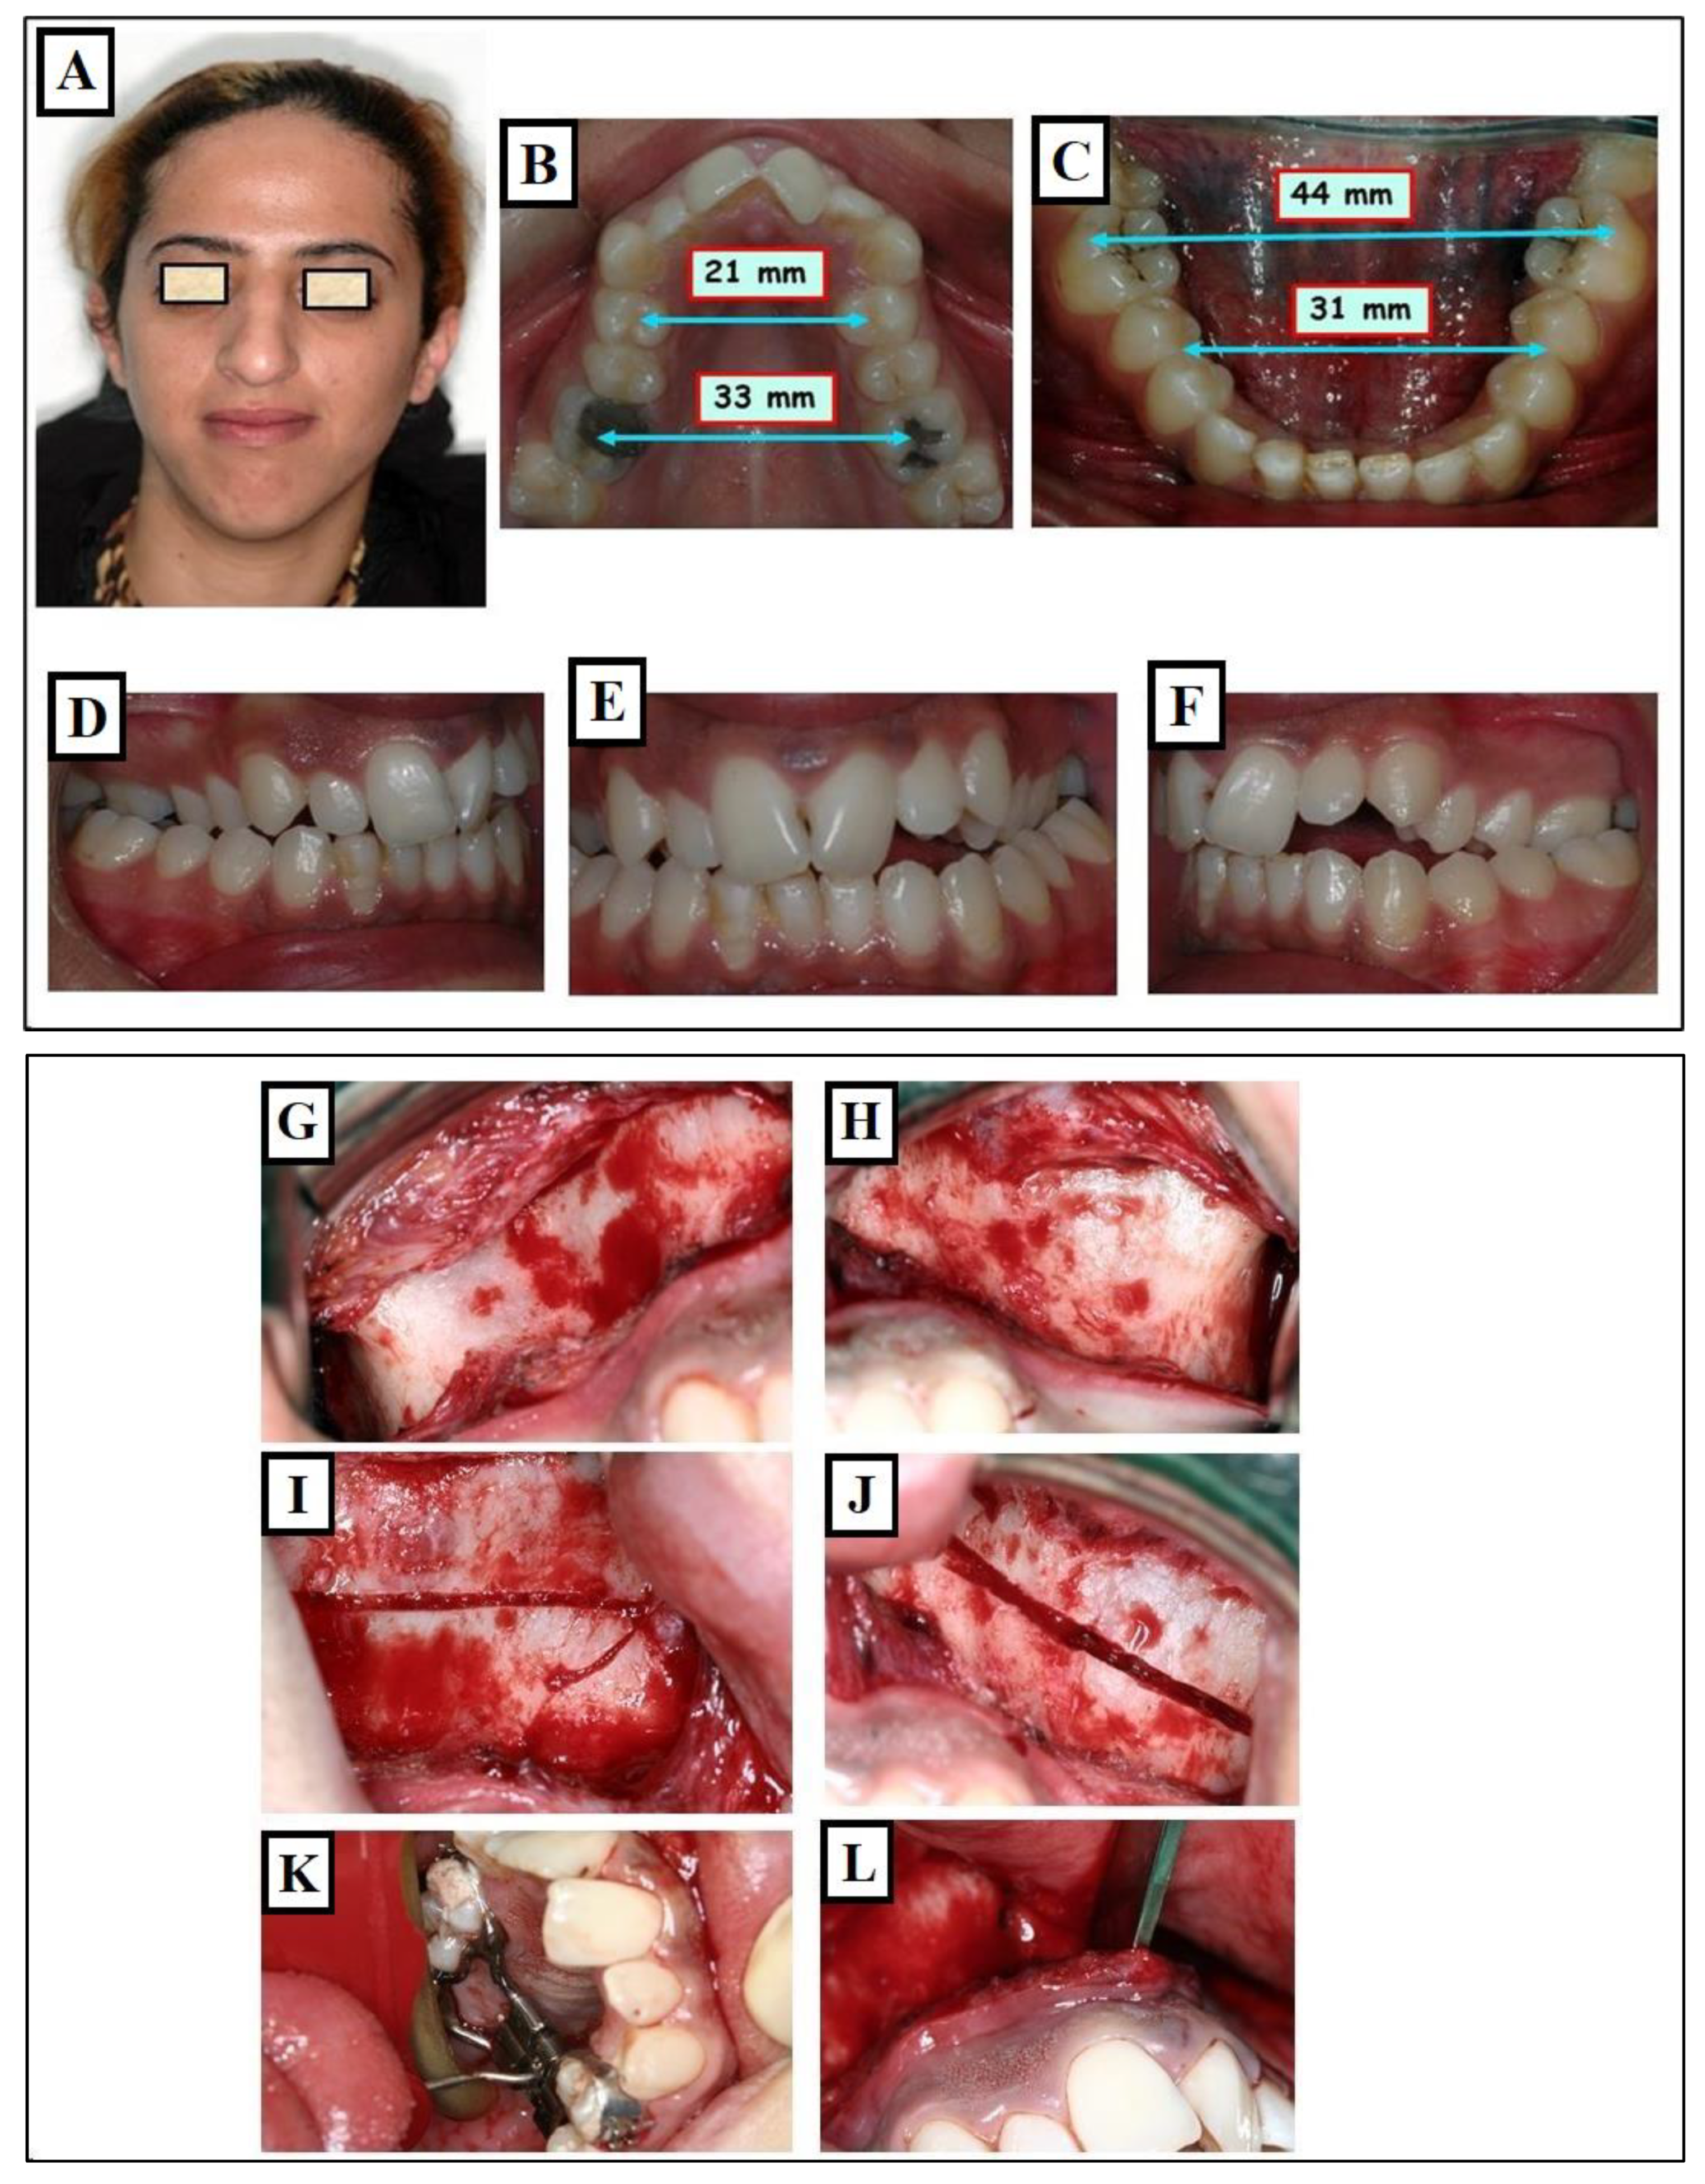

The maturity level of the individual plays a significant role when assessing the impact of Rapid Maxillary Expansion (RME) on craniofacial structures. RME treatment tends to be more effective in children than in adults. Although achieving maxillary expansion in older patients is plausible, the outcomes are not as predictable or enduring. In such instances, surgically assisted RME (SARME or SARPE) is an alternative for adolescents, and for adults, SARME remains the sole option for widening the maxilla. However, complications associated with the surgical procedure and financial constraints limit the widespread applicability of this treatment among adults. The surgical approach might be advisable in patients with extreme maxillary hypoplasia requiring extensive expansion (especially if the posterior teeth incline buccally). It also might be the preferred choice for patients who have significant gingival recession with probable dehiscence and fenestrations, and it might be beneficial for patients with sleep apnea (Figure 20A–V).

Figure 20.

Expansion of the maxilla through Surgically Assisted Rapid Palatal Expansion (SARPE). Situation before treatment: narrow face and narrow nose (A), extremely narrow upper jaw (blue arrows 21mm, 33 mm) (B) compared to the lower jaw (blue arrows 31mm, 43 mm) (C), skeletal and dentoalveolar crossbite on the right and left (D–F). Surgical assistance for maxillary expansion. Surgical separation of the bones on the maxilla was partially performed at the level of Lefort I (G–L). Maxillary expansion with the screw (M,N). Cone-beam computed tomography (CBCT) after expansion shows the separation of Maxillary parts, as part of an examination, the amount of expansion at the bone was measured compared to the screw opening (O) and the airway the colored area represents the measured airways before and after expansion (P). Improvement in breathing and breathing disorders is expected in such patients. Condition after treatment, changes in facial width (Q), changes in jaw widths (R,S) with occlusion correction (T–V).